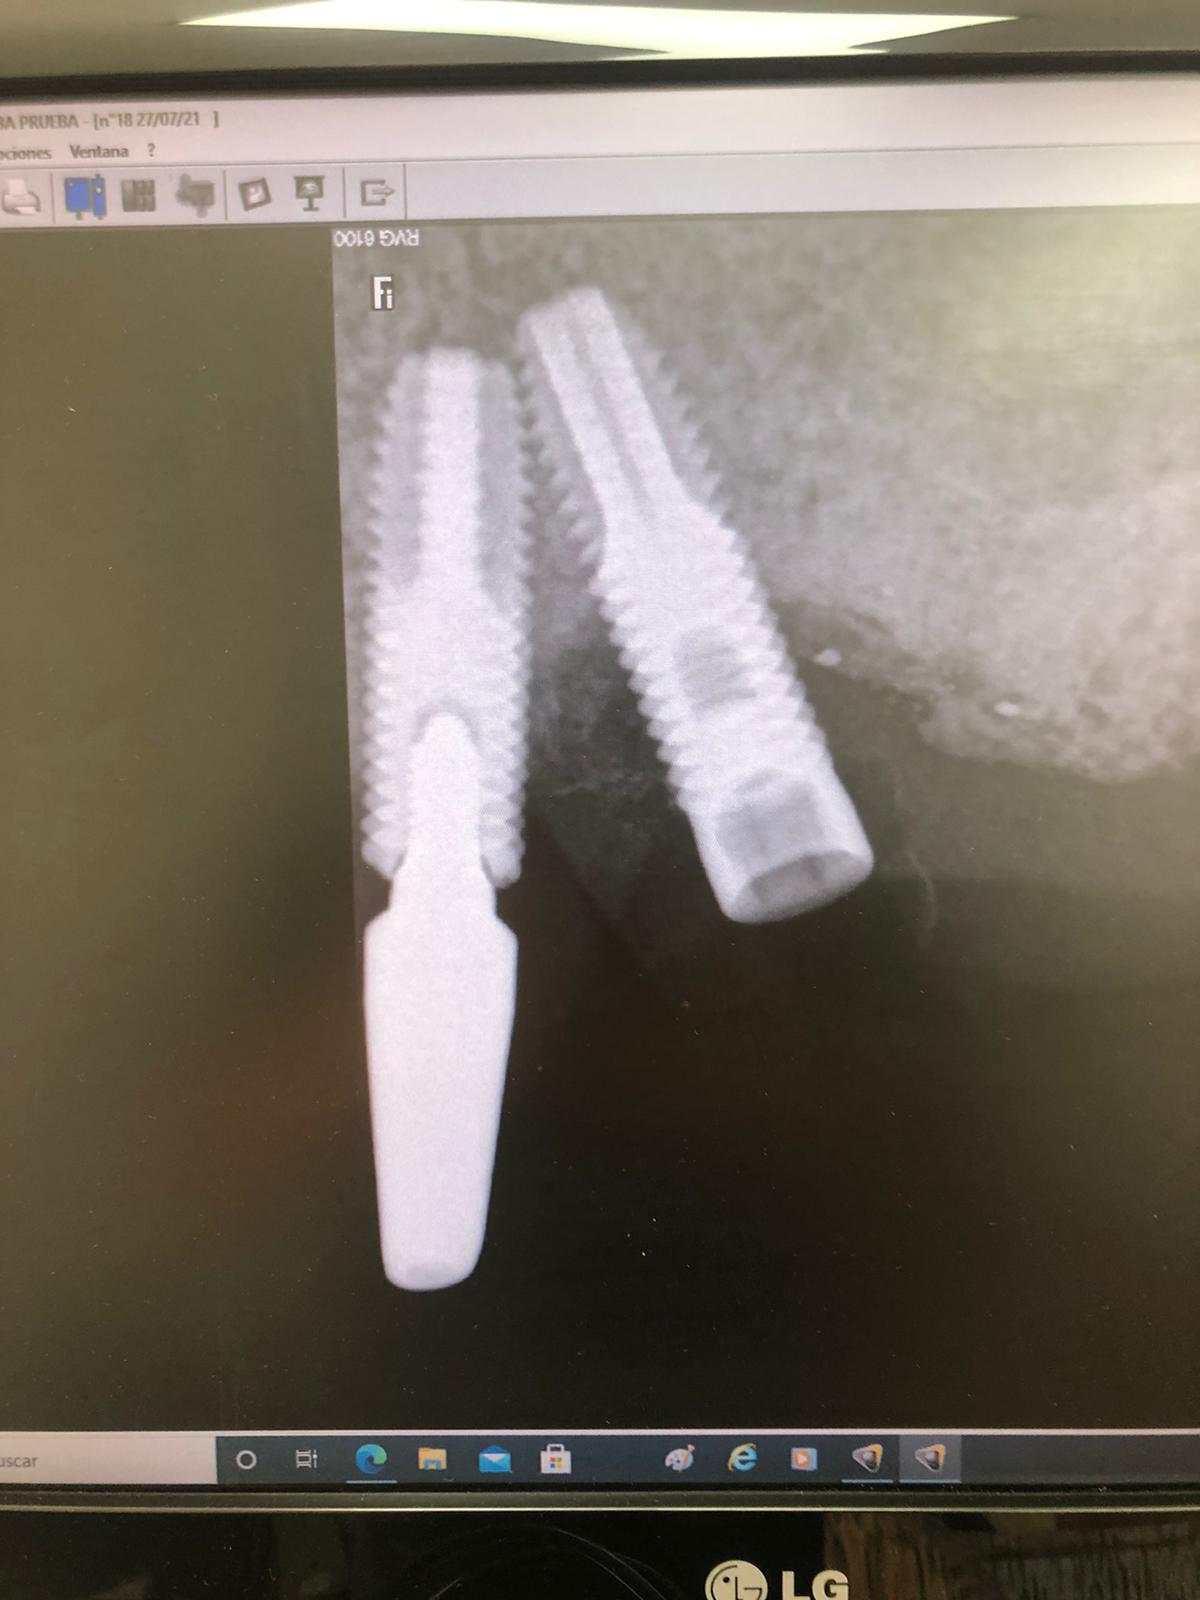

La solución a este caso fue rehacer la rosca distal rota (un poco inclinada) y después seleccionar, sellar y tallar el aditamento ASATIM. Con la sucesión de imágenes se comprende cómo se rehace una rosca:

SELECCIÓN DEL ADITAMENTO ANGULADO MACIZO DE POSICION ROTACIONAL: 60º

La flecha negra es la posición rotacional: 0 grados del aditamento tanto en la caja Asatim como el aditamento que está instalado en el implante. Hemos de seleccionar otro aditamento que su posición rotacional esté siguiendo la flecha verde y este ha sido un aditamento de posición rotacional: 60 grados: Este aditamento angulado que la parte angulada está mirando hacia Mesial (POSICIÓN ROTACIÓNAL: 60grados) es el correcto.